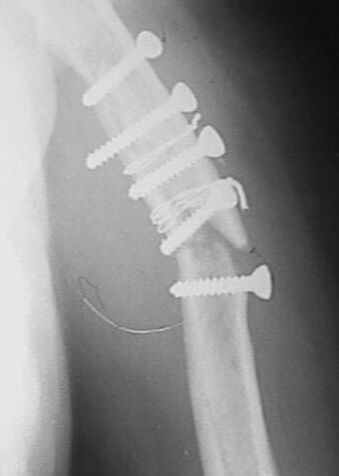

Больная оперирована в апреле 2002 г, иммобилизация в течение 3 месяцев. После операции были явления неврита лучевого нерва, которые в последующем исчезли. Во время проведения ЛФК отмечает появление болей. В настоящий момент имеется патологическая подвижность в месте перелома, деформация плеча. У нас мнения разделились в тактике дальнейшего ведения.

1. провести репозицию закрытую и продолжить иммобилизацию гипсовой повязкой. мотивируя опасностью повторного повреждения лучевого нерва при повторной операции. 2. провести открытую репозицию, удаление фиксаторов, остеосинтез накостный костной пластикой. 3. репозиция, фиксация отломков аппаратом внешней фиксации спицестержневого типа.